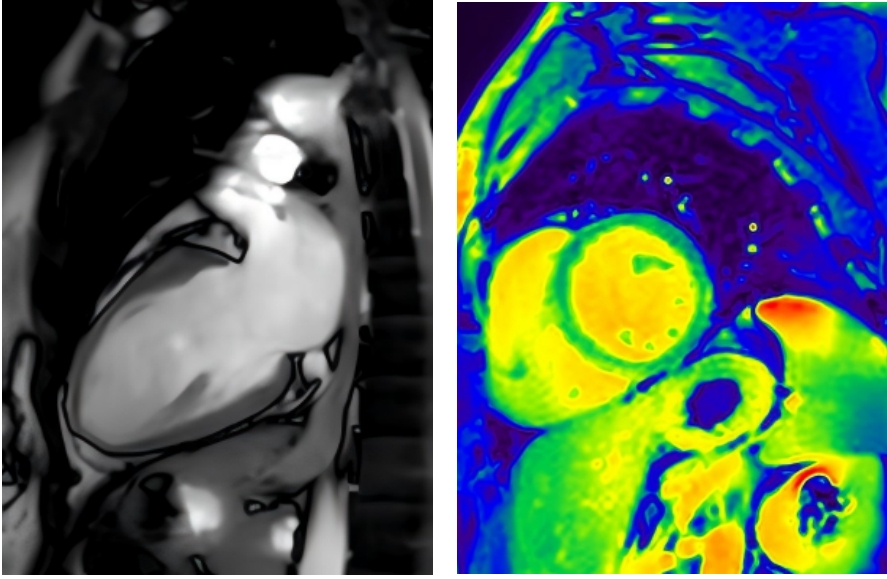

株洲市三三一医院专家介绍,磁共振利用磁场和无线电波,让人体心脏组织里的水分子(主要是氢质子)“唱歌”,不同的组织(如心肌、血液、脂肪、疤痕)“唱出的歌声”各不相同。磁共振机器接收这些信号,经过复杂的计算机处理,最终构建出精细的心脏图像。

(▲磁共仪呈现的心脏影像)